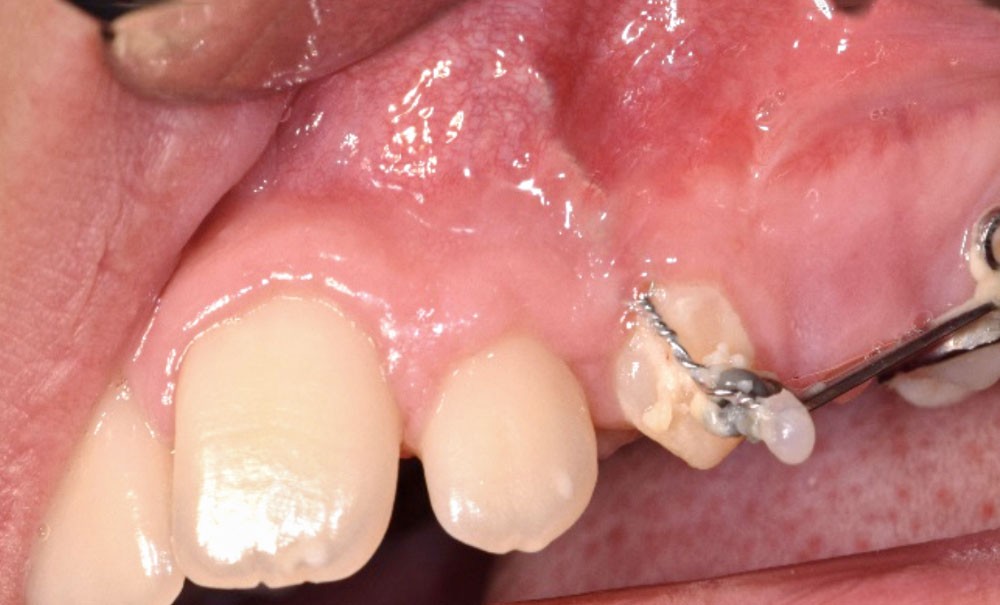

La thérapeutique orthodontico-chirurgicale est à ce jour le gold standard de la prise en charge des canines incluses. Le but est de les tracter sur l’arcade après l’aménagement de l’espace nécessaire. La dent ayant initialement une position ectopique, le trajet de repositionnement orthodontique peut conduire à des complications à long terme sur le plan parodontal [5]. En effet, une dent doit effectuer son éruption sur la crête, en présence de gencive kératinisée, ce qui permet un maintien de l’hygiène et par conséquent une santé parodontale nécessaire à la survie de la dent sur l’arcade à long terme [6, 7].